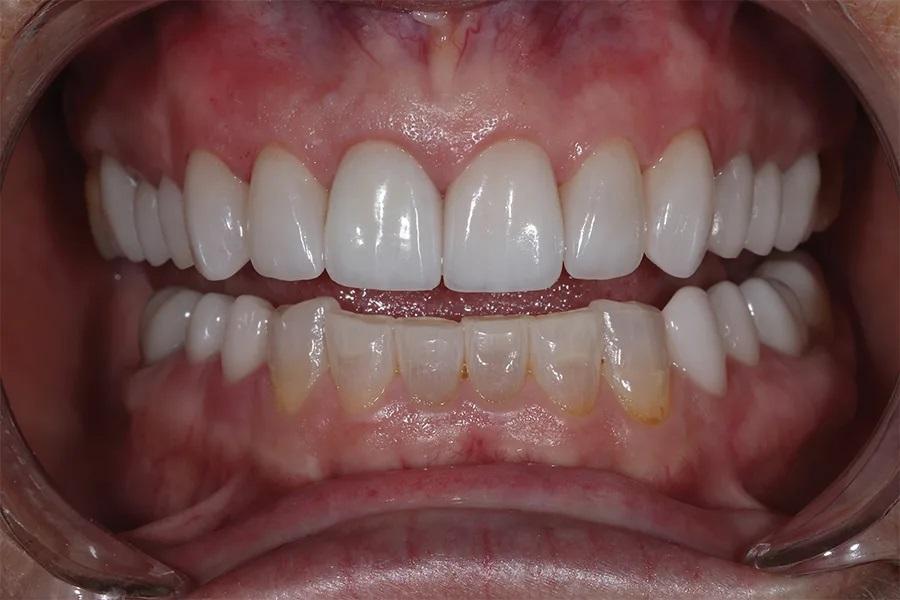

Окклюзия была повторно проверена, откорректирована и отполирована. Были достигнуты одновременные, двусторонние и равномерные по интенсивности контакты в области боковых зубов (фото 9 и фото 10). Пациентке был назначен повторный прием через 1 месяц для оценки окклюзии с точки зрения функции и комфорта.

Фото 9. Крупный план с установленными реставрациями в боковых отделах. Новый ВРО отчетливо визуализируется: режущие края верхних зубов располагаются выше фасеток износа на вестибулярной поверхности нижних резцов.

Фото 10. Вид реставраций боковых зубов после лечения при ретракции, демонстрирующий расширение буккального коридора.